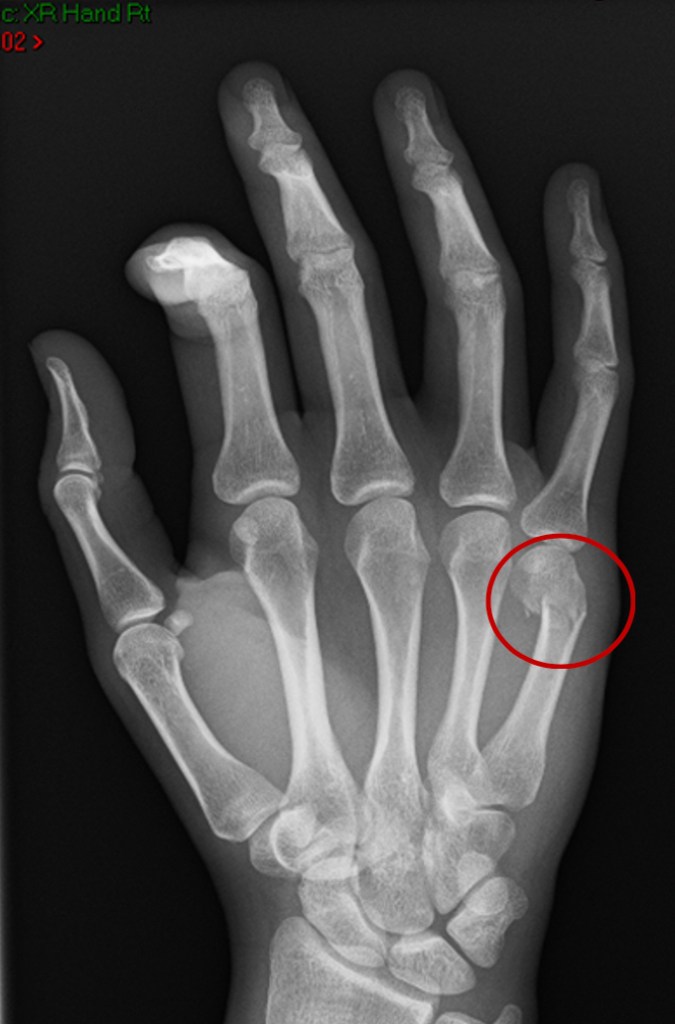

The diagnosis is made clinically. There is swelling and tenderness over the metacarpal, and the normal contour of the metacarpal head is lost when the fingers are curled into a fist. An xray will confirm the diagnosis.

A fracture of the metacarpal ALMOST ALWAYS results in loss of the knuckle, or a dropped knuckle. This looks obvious when the hand is brought down into a fist, and there is a lump over the back of the hand at the level of the broken bone. This is called a malunion.